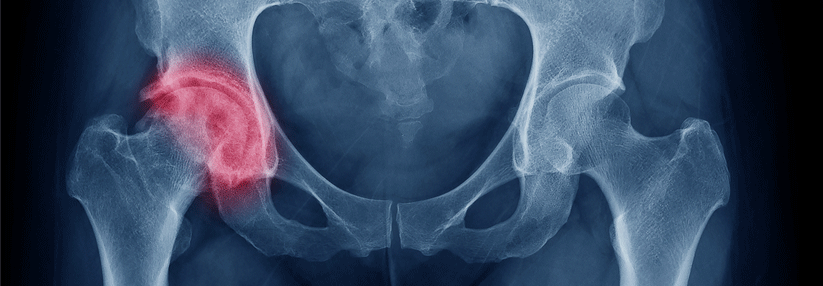

Osteoporose ist keine Frauenkrankheit, betonte Professor Dr. Maria Luisa Brandi, Endokrinologische Abteilung der Medizinischen Klinik der Universität Florenz. Millionen von Männern leiden ebenso unter der Knochenschwäche und den Folgen der Brüche – insgesamt betreffen etwa 30 % der Hüftfrakturen Männer.

Im Vergleich zu Frauen brechen ihre Knochen jedoch erst später: Ab einem Alter von etwa 60 Jahren steigen die Raten von Hüft-, Handgelenks- und Wirbelkörperfrakturen deutlich an. Weil Männer zum Zeitpunkt ihrer osteoporotischen Fraktur älter sind als Frauen, haben sie meist auch mit schwereren Folgen zu kämpfen. So zeigen Studien, dass 37 % der Männer das erste Jahr nach ihrer Hüftfraktur nicht überleben und bei den Übrigen die Lebensqualität deutlich reduziert ist.

Im Gegensatz zu den Frauen ist die Osteoporose bei Männern nur zu etwa einem Drittel primär, d.h., entweder idiopathisch oder altersbedingt. Die Mehrzahl der Fälle (65–70 %) ist sekundär. Mögliche Ursachen reichen von endokrinen Erkrankungen über Medikamente bis hin zu Lebensstilfaktoren (siehe Kasten). Zudem ergab eine Untersuchung aus dem Jahr 2016, dass neben Alter, vorangegangenen Frakturen und den schon bekannten Risikofaktoren noch weitere Umstände die Gefahr einer Hüftfraktur zusätzlich steigern können: Dazu gehörten z.B. eine hohe Statur, kognitive Einschränkungen, Scheidung und ein schlechtes Abschneiden im Aufstehtest.